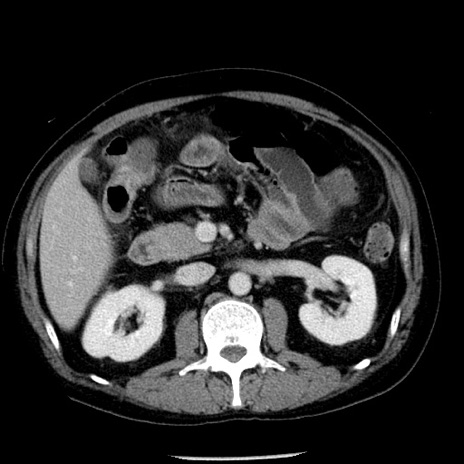

症例29(横断像)

【症例】40歳代男性

【現病歴】2日前から胃痛あり。徐々に周期的な激痛に変化した。本日になっても激痛があるため受診。

【身体所見】意識清明、BT 38-39℃台あり、腹部:膨満、やや硬、右下腹部に圧痛あり。

【データ】WBC 8500、CRP 23.26